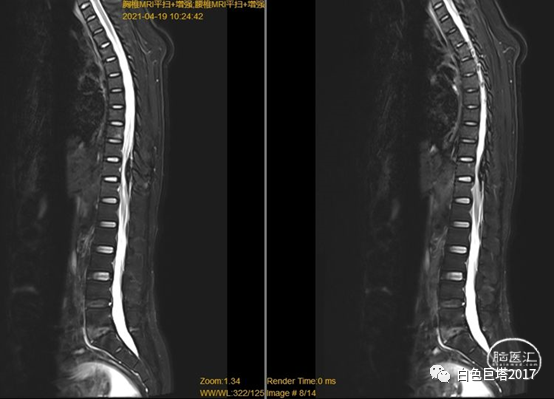

考虑患者体格检查结果与既往病史不符合,患者语言功能障碍,不能很好配合检查。请我科会诊,急诊完善胸腰椎磁共振平扫+增强。

图示:T1

图示:T2,红色箭头所示T10-T12水平椎管内硬脊膜外低信号。

图示:T2压脂像,T8椎体血管瘤。

T2水平面可见相应节段脊髓明显受压。